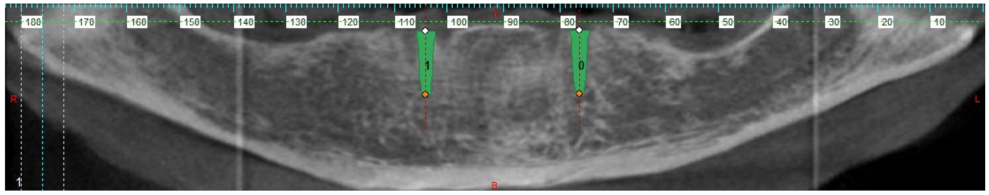

2. Materials and Methods

3. Results